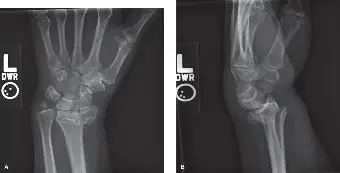

التصوير بالأشعة السينية (X-ray)

تُعد الأشعة السينية هي الخطوة الأولى والأكثر أهمية في تشخيص كسر عظم الكعبرة البعيد. يتم أخذ عدة صور من زوايا مختلفة (أمامية خلفية، جانبية، مائلة) لتقديم رؤية شاملة للكسر.

- المنظر الأمامي الخلفي (PA): يقيّم ميلان الكعبرة وطولها.

- المنظر الجانبي: حاسم لتقييم ميلان راحة اليد (Volar Tilt) ووجود تفتت خلفي أو أمامي.

- المنظر المائل: يوفر تفاصيل إضافية عن مدى الكسر.

تساعد هذه الصور الدكتور هطيف في تحديد مدى إزاحة الكسر، ما إذا كان الكسر داخل المفصل أو خارجه، ووجود أي تفتت.